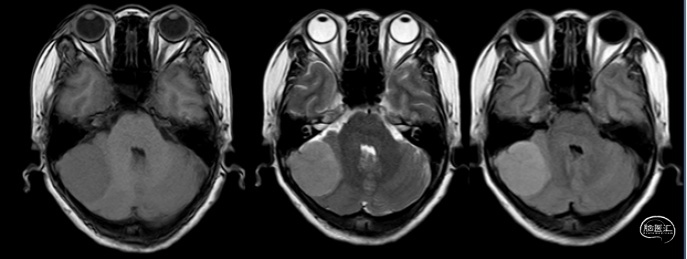

作者:左赋兴 万经海

患儿9岁,男性,两周前突发剧烈头痛呕吐晕厥,当地医院考虑松果体区占位病变致梗阻性脑积水。患儿后于我院就诊,查体见双眼上视不能。头颅MRI明确三脑室后部混杂信号病变,中脑顶盖和四叠体受压下移,增强扫描见肿瘤显著不均匀强化,与大脑内静脉和Galen复合体关系密切;头颅CT提示肿瘤密度不均伴钙化,幕上脑室系统显著扩大。